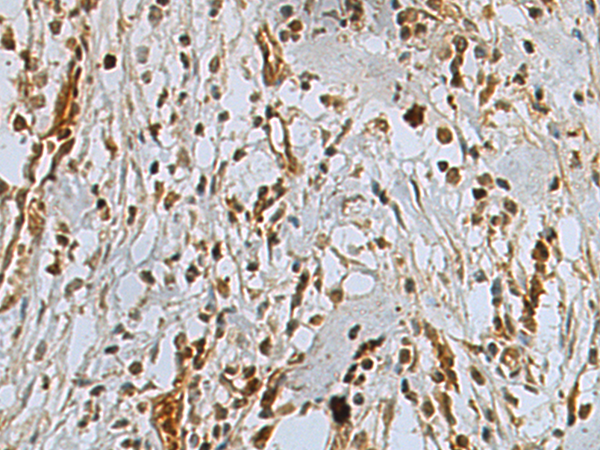

IHC positive control: |

Human gastric cancer |

IHC Recommend dilution: |

50-200 |